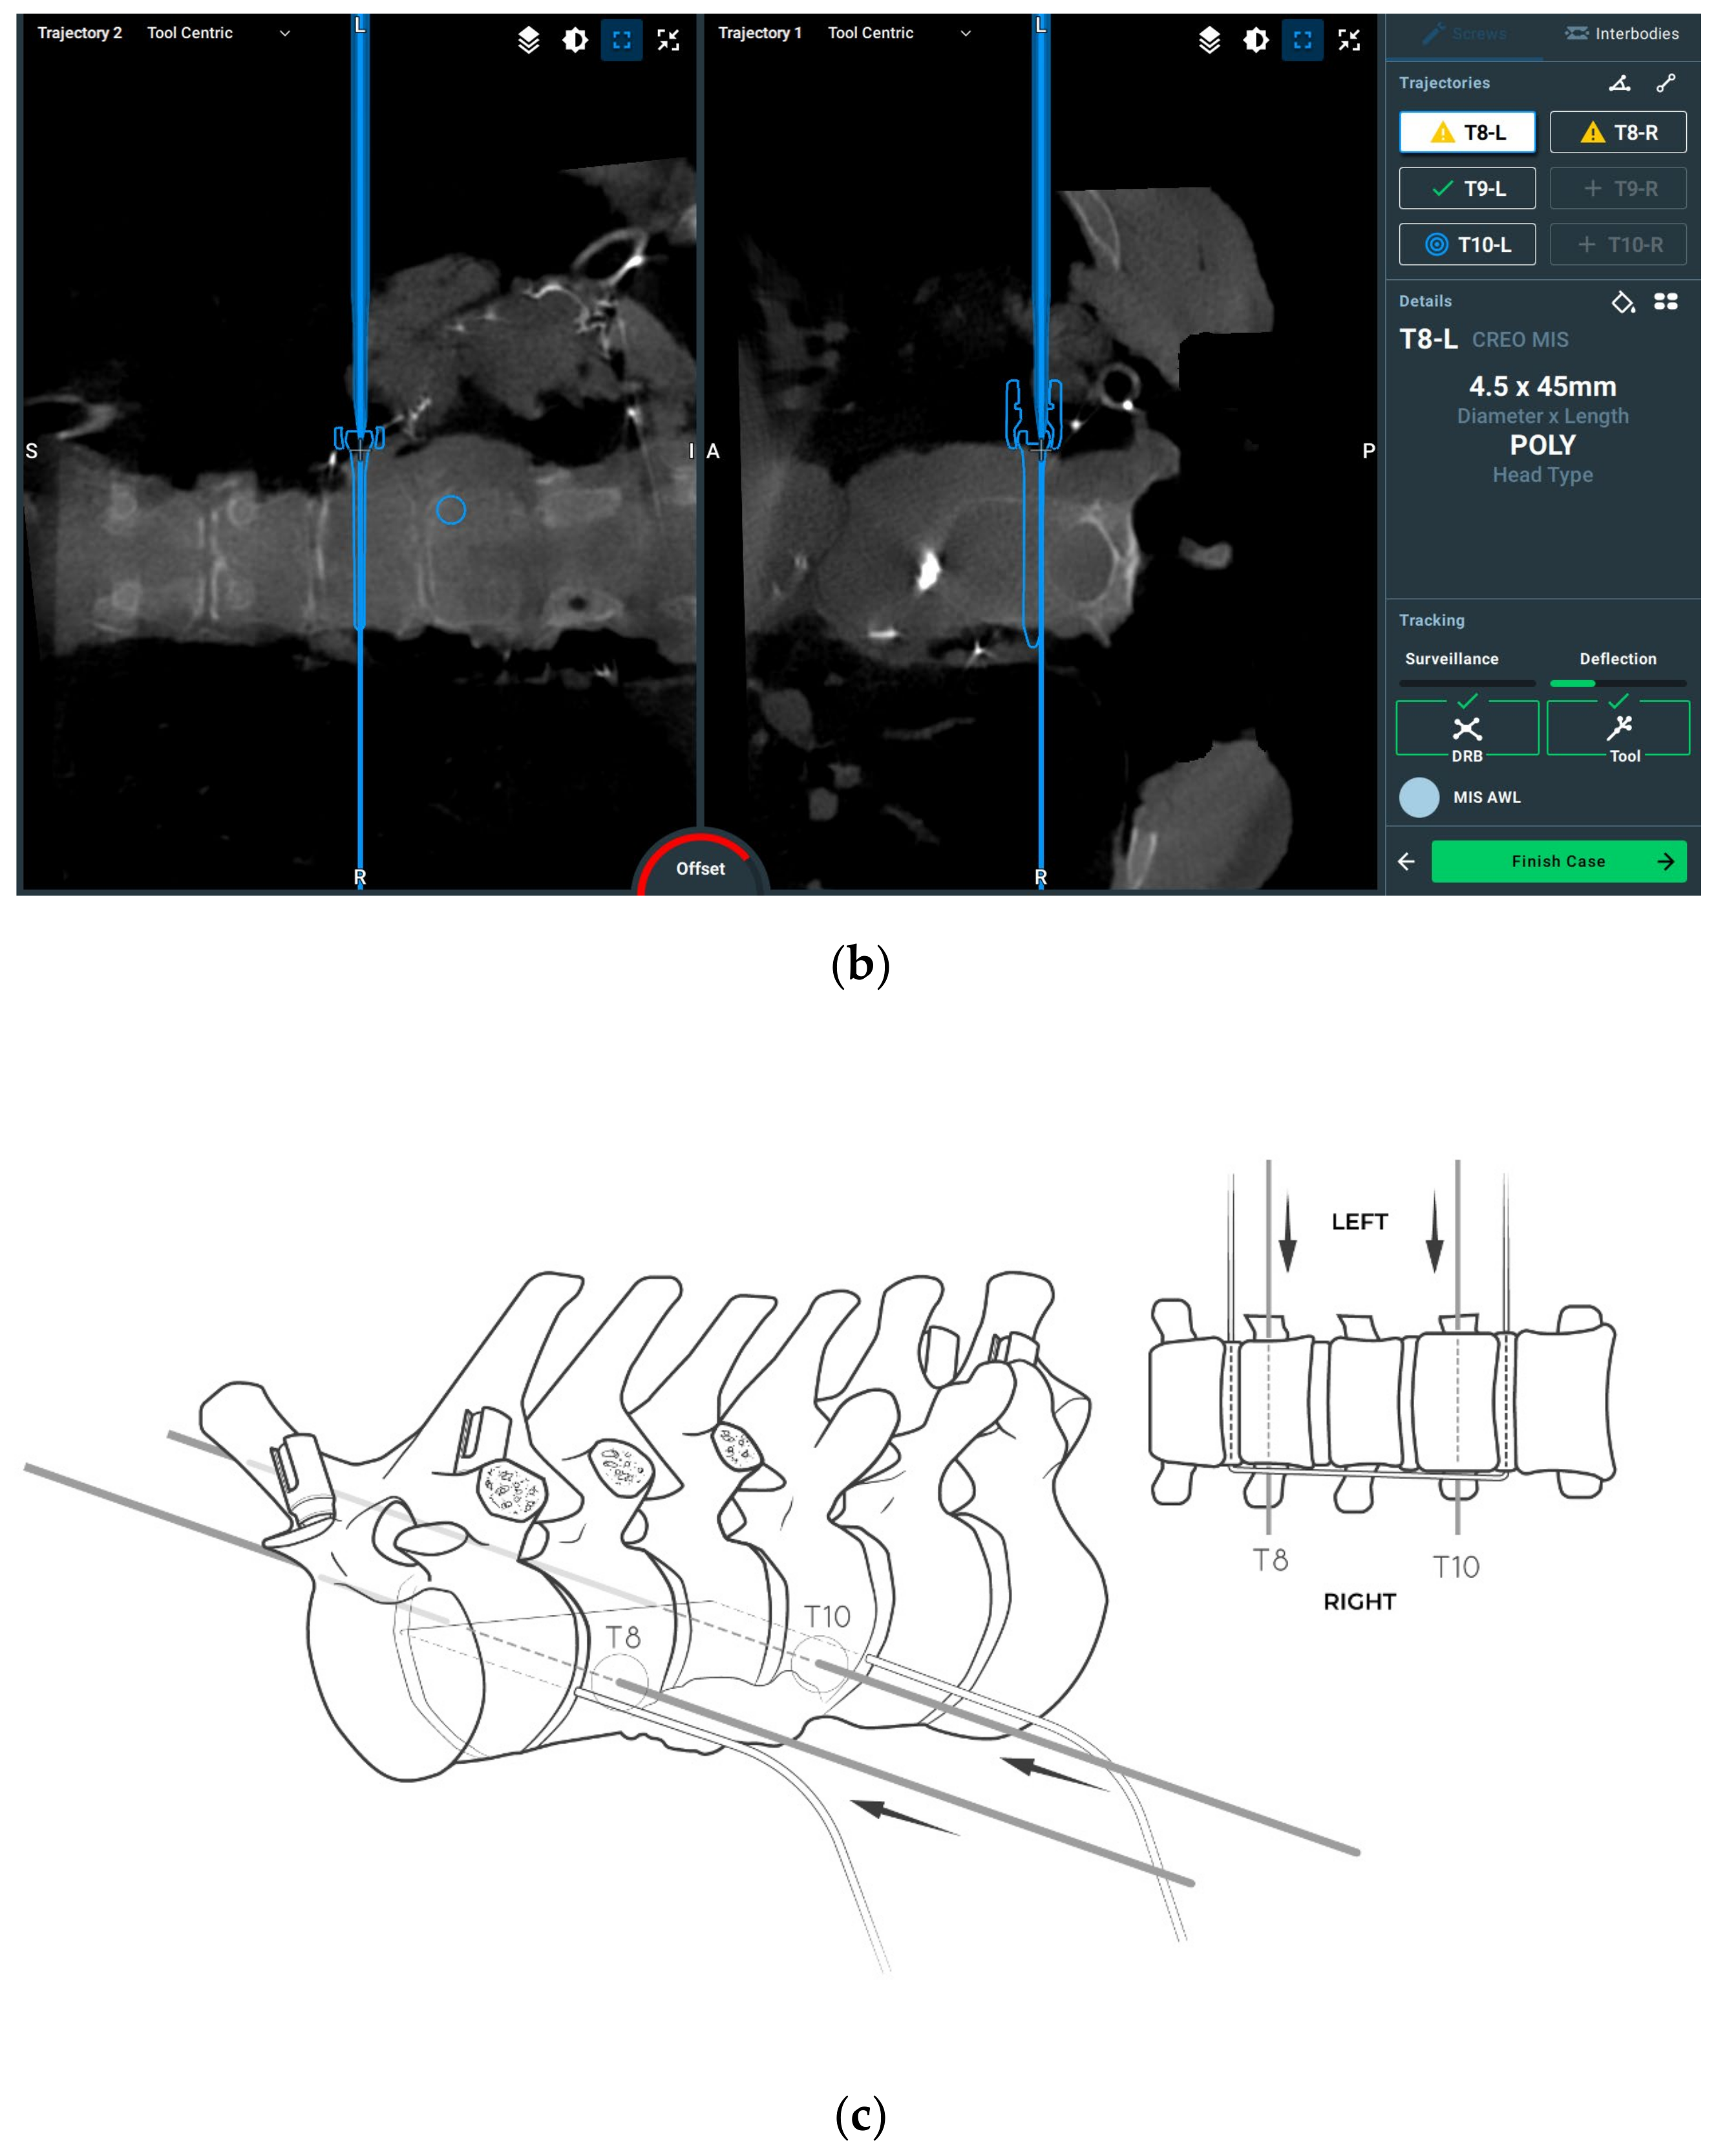

2.3. Surgical Planning

2.4. Surgical Procedure